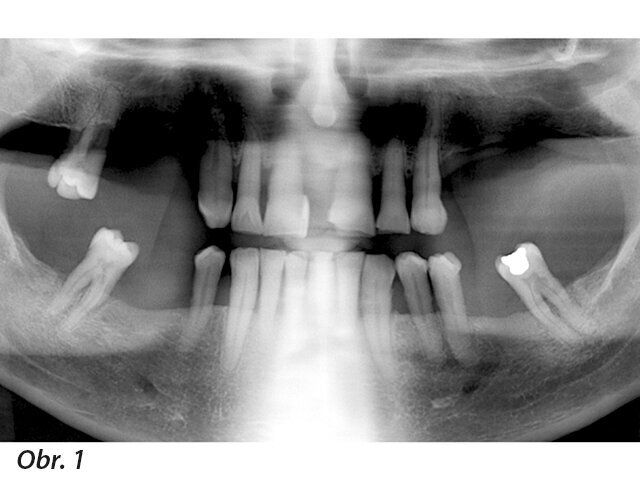

Iniciální situace

68letý pacient, bez lékařsky relevantní anamnézy a se zoufalým stavem chrupu, k nám byl delegován svým parodontologem. Byly pořízeny panoramatické CT snímky, na základě kterých jsme vyhodnotili dostupnost, dispozice a hustotu kostí (obr. 1 a 2). Po projednání různých možností léčby a s ohledem na celkovou klinickou, sociální a finanční situaci pacienta byla implantologická léčba s fixní dlouhodobě provizorní náhradou ve stejný den první volbou jak pro stomatologický tým, tak pro pacienta.